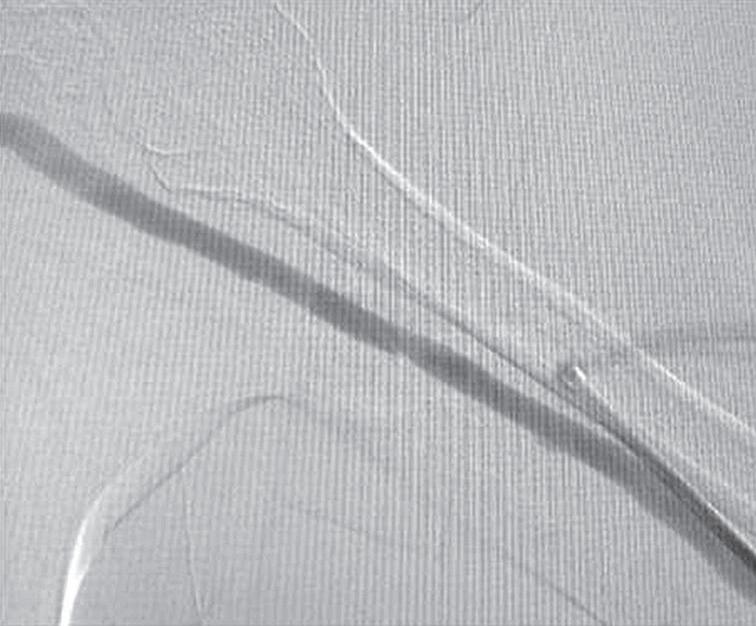

As fístulas arteriovenosas (FAV) nativas funcionais são consideradas os acessos vasculares de escolha para a realização de hemodiálise (HD) em decorrência de menores custos, melhores taxas de perviedade, menor morbidade e menores taxas de mortalidade quando comparadas com outras modalidades de acesso vascular.1-5 Entretanto, após a confecção de uma FAV, é necessário um período de algumas semanas para que o acesso possa ser utilizado. Esse tempo é conhecido como período de maturação do acesso. Apesar dos resultados superiores das FAV, 23% a 46% desses acessos apresentam problemas para atingir um diâmetro e fluxo adequado para sustentar diálise efetiva.5-8 Esses problemas são descritos na literatura médica como falha de maturação do acesso.9 Recentemente, alguns autores têm recomendado o salvamento de uma FAV não maturada por meio de intervenções endovasculares. Essas intervenções são conhecidas como maturação assistida por balão (BAM).10-12 O objetivo deste capítulo é descrever as técnicas e os resultados dos procedimentos endovasculares para promover a maturação das FAV em falência.

Figura 26.13 (A a F) Aspecto pré‑ e pós‑maturação assistida por balão superdimensionado (oBAM; do in glês, oversized balloon assisted maturation) Fístulas arteriovenosas braquiocefálica com múltiplas esteno ses (setas vermelhas), estenose justa‑anastomose (seta amarela) e importante circulação colateral (setas pretas) (A e B) Arco venoso cefálico (C) Aspecto pós‑oBAM com balões de alta pressão 6 e 8mm (D a F)

Fonte: arquivo pessoal dos autores

pacientes foram submetidos à eco-Doppler colorido pós-operatório para a análise do diâmetro do vaso, a mensuração do volume de fluxo e a posterior canulação da FAV nos casos em que a intervenção foi bem-sucedida. Percebemos sucesso

técnico e clínico em 91% dos pacientes (Tabela 26.1). As taxas de perviedade primária em 3, 6 e 12 meses foram de 87,3%, 66,2% e 50,7%, respectivamente, enquanto as taxas de patência secundária se mostraram de 100% em três